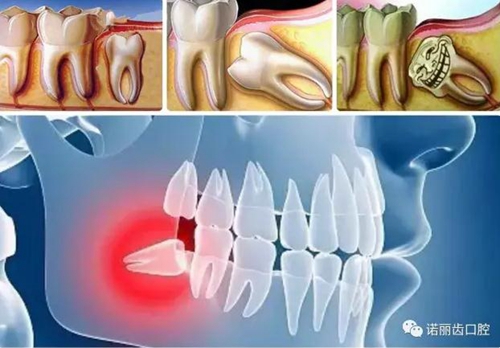

那么,如何判斷自己的智齒生長情況呢?除了有明顯的疼痛感你需要做相應的處理,同時通過X線可以觀察智齒的數(shù)量和位置以及具體情況。

經(jīng)過拍片探查,確定了以下情況的,那么,果斷的,禍患不可留啊:

智齒蛀牙

如果智齒出現(xiàn)比較深的蛀牙,特別是需要根管治療的,一律建議拔除。

造成鄰牙病變

如果生長空間不足,智齒會使勁兒頂住相鄰的牙齒繼續(xù)生長,可能導致兩顆牙齒都保不住,此時建議拔除。

空間不足引起冠周炎癥

如果智齒生長空間不足,在智齒生長過程中,會出現(xiàn)比較嚴重的牙齦腫脹、牙齒疼痛等癥狀。

沒有對咬牙

如果智齒的對面沒有相抗衡的智齒來對咬的話,有時會發(fā)生智齒過度萌發(fā)伸長的現(xiàn)象,進而影響咬合,此時應拔除智齒。

阻生智齒

這是比較常見的一種問題,該種智齒通常埋在齒槽骨的里面,如果經(jīng)常發(fā)生炎癥,或是診斷會有病灶發(fā)生的時候,就必須拔除。